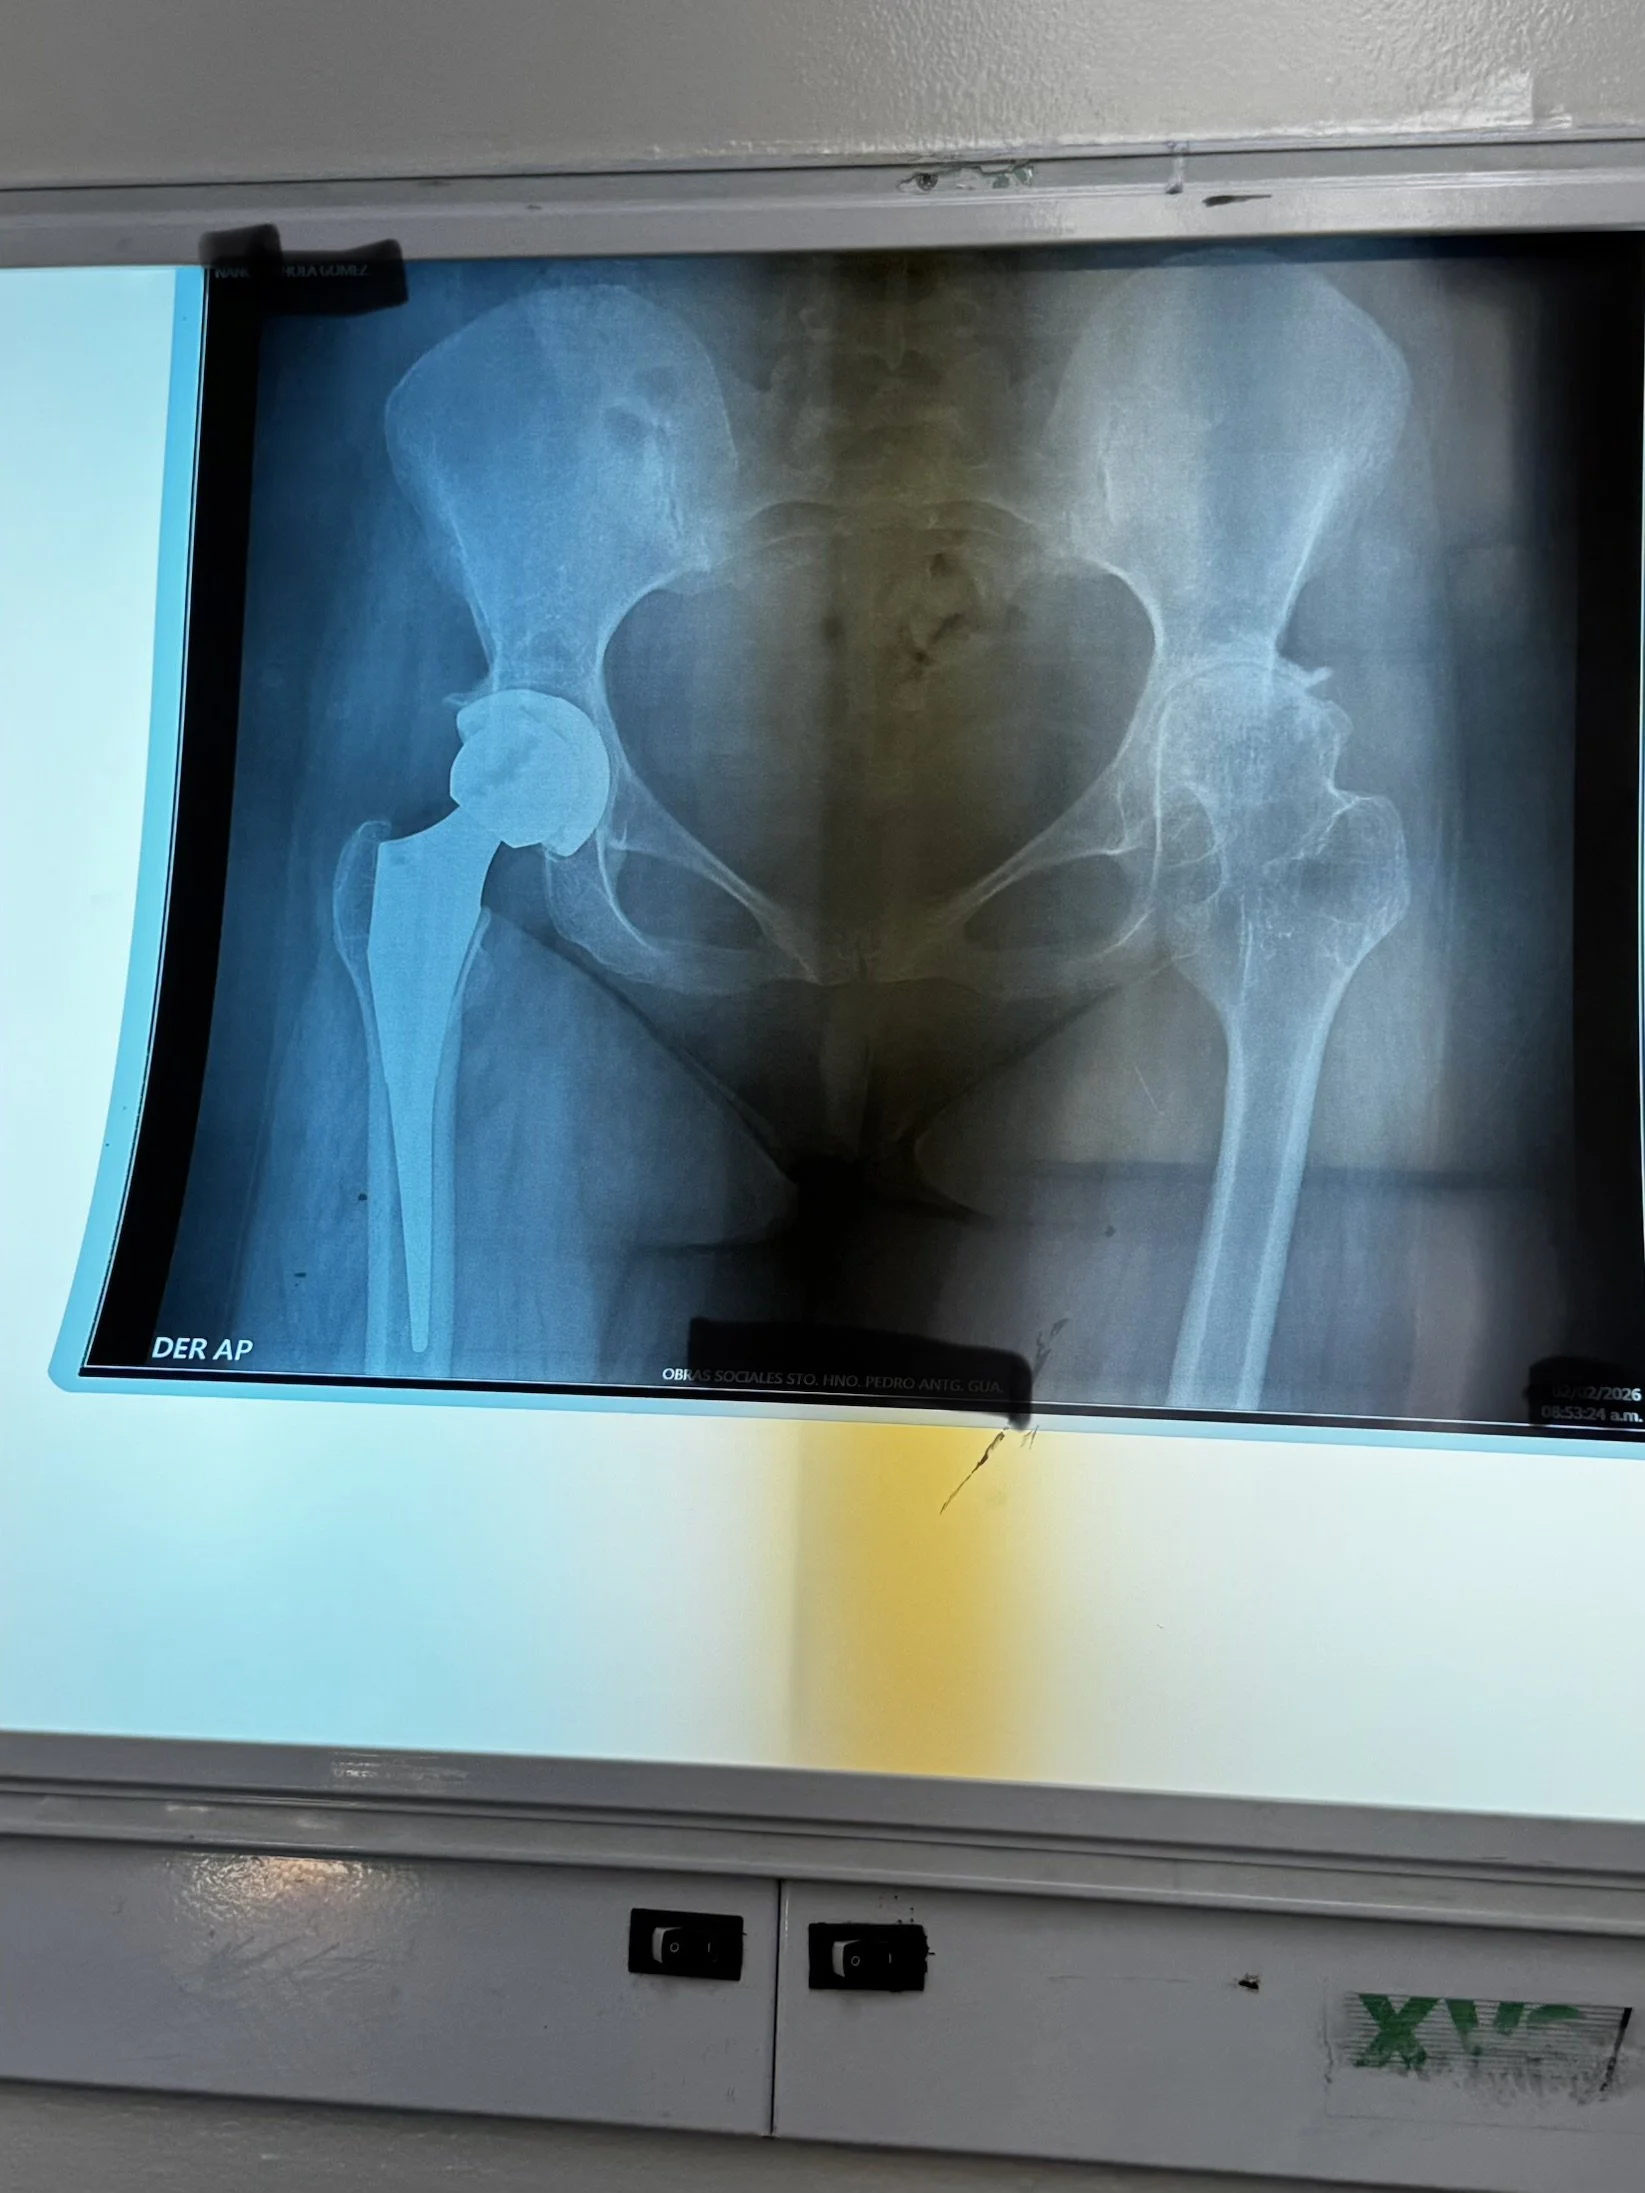

Patient Stories:

Blessings and Gratitude. Our patients are blessings to us. We marvel at their calm patience. Some of them have lived lives with great difficulty for many years. These procedures will change them, their families, and their communities.

Abel traveled with his son for 2 days to get to Antigua for his knee replacement. For 10 years, he has suffered with great pain. Yesterday, he received a new right knee. This morning, he walked out of the hospital for his 2-day trip home in hopes of getting back on his tractor at his farm.

Alejandro, our 28-year-old hip patient from Monday, also went home today. We discovered her grandmother, who had been by her side yesterday after surgery, had been cooking all day so the family could celebrate her homecoming.